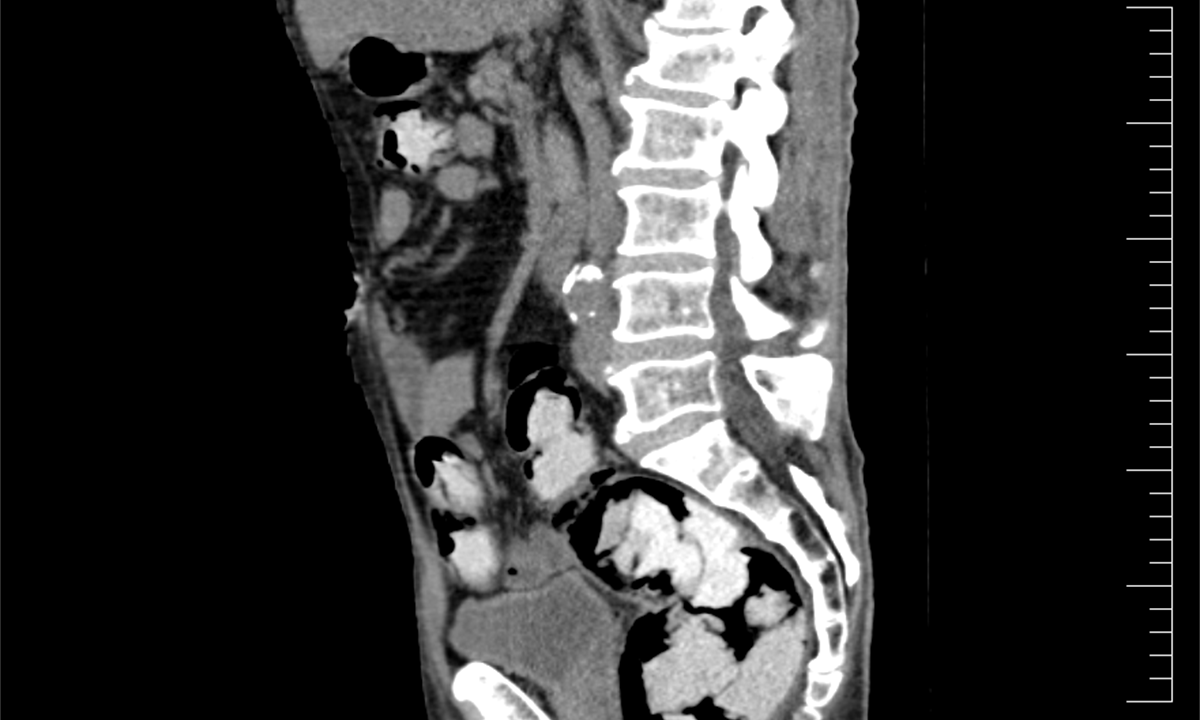

Ke kontrole byl polykač celníky vytipován na základě provedené rizikové analýzy daného letu. Prvotní podezření na pašování drog celníkům potvrdily kontrolní stěry z rukou pašeráka.  Při důkladné kontrole jeho zavazadel a osobní prohlídce nebyly drogy nalezeny, proto bylo provedeno následné CT vyšetření, které podezření potvrdilo.

Postupně z těla pašeráka vyšlo 112 kontejnerků naplněných bílým práškem. Chemická látka při provedení detekční zkoušky pozitivně reagovala jako kokain. Celková hmotnost všech kapslí je více než 1,2 kg. Určení vlastní hmotnosti a druhu zajištěné drogy je předmětem další odborné expertízy. Podle zkušeností celníků se s největší pravděpodobností jedná o velmi koncentrovaný kokain. Zda byla droga určena na český trh nebo k distribuci v jiné zemi, je předmětem dalšího šetření.